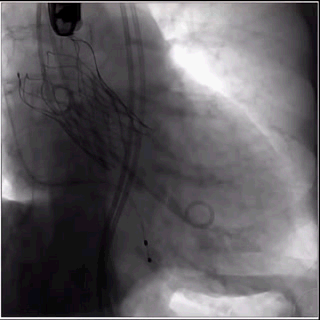

4、麻醉团队配合停止呼吸机,150次/min快速起搏下,缓慢释放瓣膜;前三分之一释放完成后,确认VitaFlow Liberty™瓣膜已经贴壁,没有发生移位的情况和趋势,随即长按电动输送系统释放按钮,一次性完成释放,整个释放过程中瓣膜没有出现位移。

瓣膜释放成功

5、撤回输送系统,造影和食道超声显示基本无反流,患者术前舒张压47/48mmHg,术后显示68mmHg,无压力差,无瓣周漏,整台手术圆满完成。

术后造影及超声检查